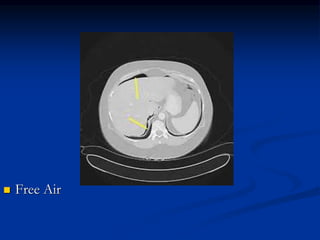

Perforated Peptic Ulcer

 Free air seen on plain radiographs or CT

Perforated Peptic Ulcer History: PUD, NSAIDS, steroids, critical illness  Exam: Severe tenderness, generalized rebound  Tympanic on percussion  Free air seen on plain radiographs or CT  Mostly treated surgically